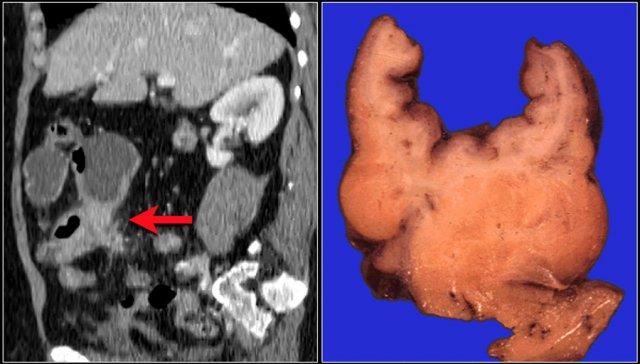

Đây là hình ảnh bệnh nhân thiếu máu cục bộ ruột do huyết khối tĩnh mạch mạc treo tràng trên – SMV (mũi tên đỏ).

Lưu ý tình trạng ứ máu tĩnh mạch trong mạc treo ruột (mũi tên vàng).